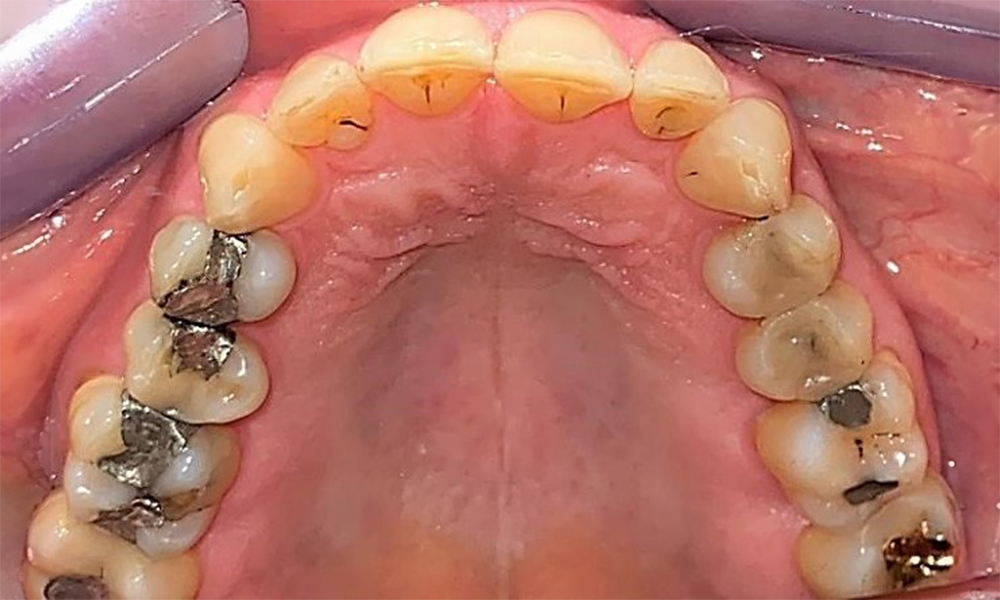

Occlusal view of the maxilla. Insufficient amalgam filling of 14 with a marginal gap.

Fig. 5 Occlusal view of the maxilla. Insufficient amalgam filling of 14 with a marginal gap. © Dr R. Krapf

The patient has a full dentition with 28 teeth, which includes amalgam and composite fillings in the molar and premolar regions. There is a visible clinical marginal gap present on tooth 14. Tooth 27 has an adequate gold inlay. There are also generalized attritions and abrasions. (Fig. 2, Fig. 3, Fig. 4, Fig. 5, Fig. 6)